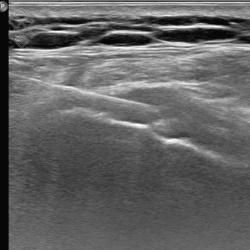

La durée de l'examen est d'environ 20 minutes. Pour repérer la zone souahitée, le radiologue fera une échographie ou une scopie. Ensuite, il effectuera une désinfection puis une anesthésie locale. Pour l'injection du corticoïde, il introduira une aiguille dans la zone repérée. Enfin, il appliquera un pansement étanche.